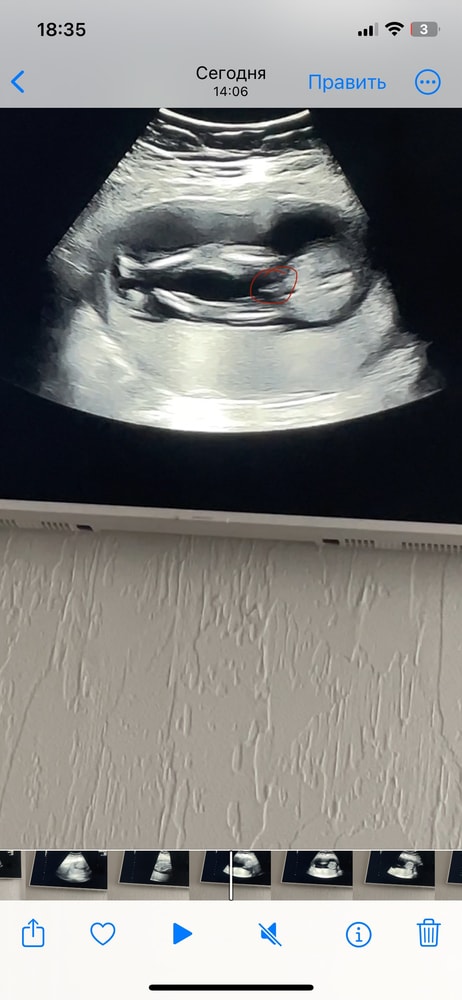

Всем привет, девочки)! Я никак не могу успокоится.. В предыдущем посте рассказала, что у врача возникли сомнения в определении пола на сроке 15 недель и 5 дней. Хотя, увидев снимок с УЗИ, для меня все стало очевидно и я была уверена в мальчике. Но смущают сомнения врача из за которых я отменила гендер пати и девочки на форумах многие пишут, что похоже на девочку. Я пересмотрела короткое видео с УЗИ, которое успела снять. Наделала скрины. Посмотрите кому не лень, на кого больше похоже? Может у вас есть похожие фото? Кто оказался? На повторное УЗИ в другую клинику записалась через неделю, но мысли продолжают одолевать 😅

Натали, с девочкой фото нет, но на экране врач показывал 2 полосочки, как у вас на втором фото, назвав это "кофейным зернышком" девчачьим

Натали, вот в каких то моментах и правда буду зернышко, а в каких-то прям очевидный писюн😂 Ох уж этот малыш) С первым ребенком на этом сроке все было понятно и очевидно

Я бы сказала, что мальчишка... У меня примерно такой же снимок есть, где все вообще без вопросов... Писюль висит прям во всей своей красе